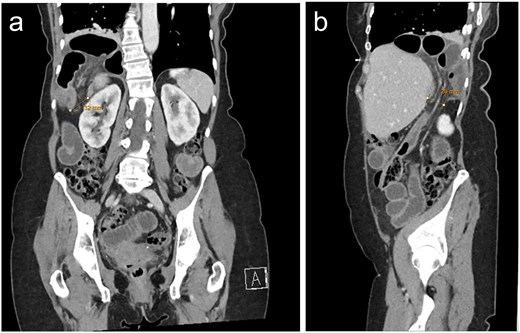

A 70-year-old female presented to the Emergency Department at our quaternary hospital with a 2-day history of abdominal pain, vomiting and obstipation. Her background was significant for hypertension and an appendicectomy at the age of 6. Seven years prior, the patient sustained right sided rib fractures following a fall. A computed tomography (CT) scan of the chest, abdomen and pelvis demonstrated a large right-sided diaphragmatic hernia containing incarcerated small bowel with reduced mucosal enhancement concerning for evolving ischaemia (Fig. 1). A diagnosis of delayed traumatic diaphragmatic hernia was made, and the patient was booked and consented for emergent laparoscopy.

CT with a) coronal and b) sagittal slices demonstrating right sided posterolateral diaphragmatic defect containing incarcerated small bowel.